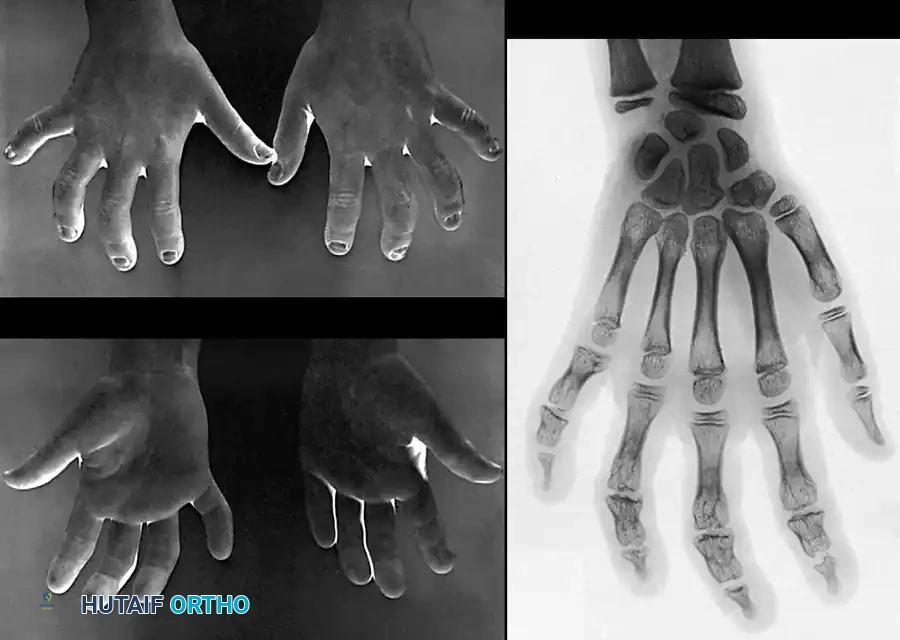

Children sustaining severe frostbite injuries face the unique and devastating complication of premature physeal arrest. As reported by Bigelow and Ritchie, the cartilaginous growth plates are highly susceptible to cold-induced chondrocyte necrosis.

Image

The index and little fingers are statistically involved more frequently than the middle and ring fingers, while the thumb is typically spared due to its robust vascular supply and protected anatomical position. The disturbance in longitudinal growth develops insidiously over years. Later in life, corrective osteotomies or lengthening procedures may be required to address severe angular deformities; however, these interventions should be delayed as long as possible to allow for maximal skeletal maturation.